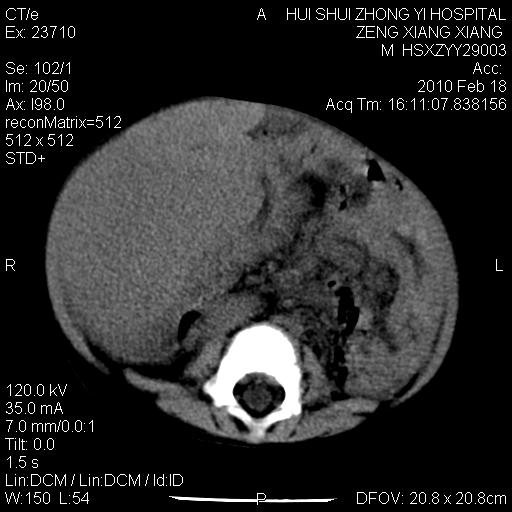

标题: PED3106:男,2岁,腹胀1月。 [打印本页]

标题: PED3106:男,2岁,腹胀1月。

定位腹膜后,肾上腺来源;

定性:恶性神经源性,肾上腺神经节母细胞瘤可能性大。

鉴别:肝母、肾母、肝脏中胚层错构瘤。

依据:年龄、有钙化,肾脏及肝脏受压移位。

肝母细胞瘤可能性大,右肾形态大体可见,不支持肾母细胞瘤,右肾移位不明显,肾上腺神经母细胞瘤可能性不大。